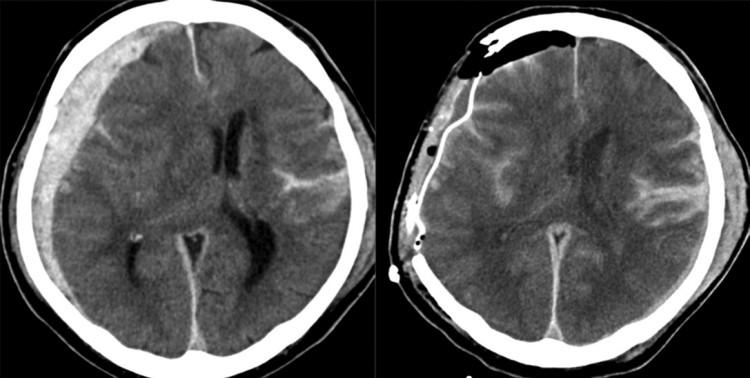

硬膜外血肿与急性硬膜下血肿在ct上的区别

急诊头部ct扫描显示,右侧急性硬膜下血肿,脑挫伤和蛛网膜下腔出血

硬膜外和硬膜下血肿图

硬膜外和硬膜下ct区别